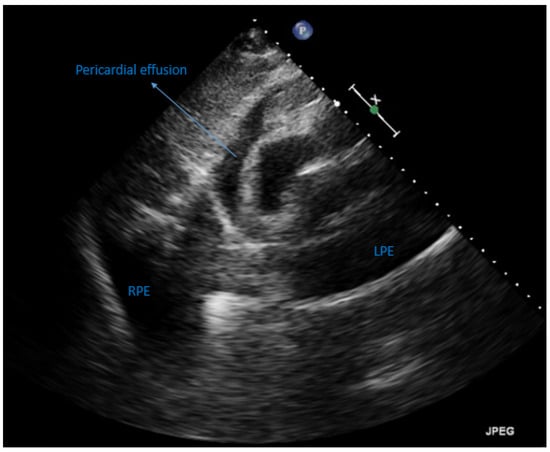

2. Case Presentation